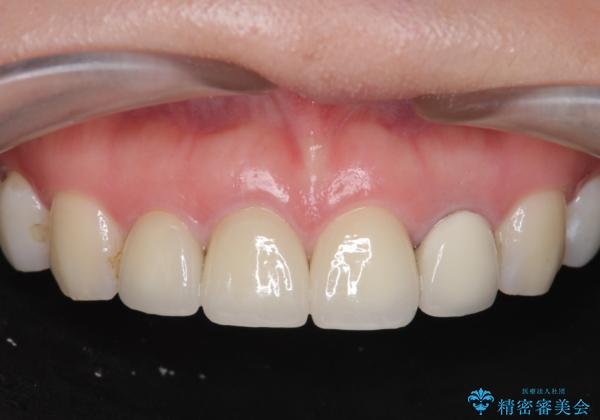

- 37万円(仮歯×3・ファイバーコア×2・ジルコニアクラウン×3)費用は治療当時の料金となります

審美的なジルコニアクラウンを装着し、審美性が回復されたと満足いただくことができました。